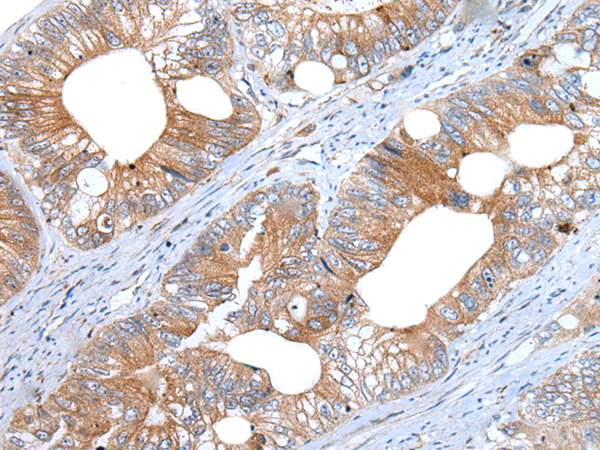

分类: 科研抗体货号: P12899别名: IGI; IGVPB; VPREB; CD179a应用: IHC反应种属: Human